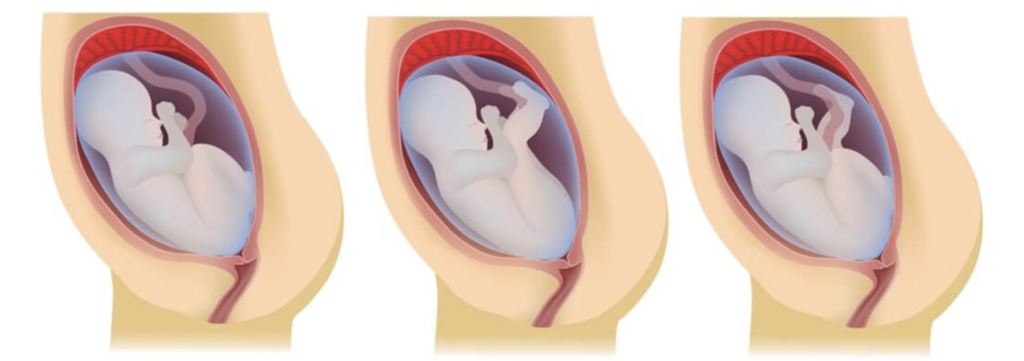

Como descobrir se o bebê está pélvico? Geralmente, o diagnóstico é feito durante o pré-natal, por volta da 32ª a 36ª semana de gestação. Seu médico ou enfermeira obstétrica pode identificar a posição através da palpação da barriga, sentindo a cabeça do bebê na parte de cima do útero e as nádegas ou pés na parte de baixo.

Para confirmar, a ultrassonografia é a ferramenta mais precisa. Ela não só verifica a posição exata, como também avalia o tipo de apresentação pélvica, a quantidade de líquido amniótico e a localização da placenta, informações vitais para planejar os próximos passos. Um bom diagnóstico é o primeiro passo para um plano de parto seguro.

Técnicas para Virar o Bebê

Pode confessar, a primeira coisa que vem à mente é: ‘como fazer o bebê virar?’ E a boa notícia é que existem, sim, algumas estratégias. Uma das mais conhecidas é a Versão Cefálica Externa (VCE), um procedimento médico realizado por um obstetra experiente, geralmente a partir da 36ª semana. Nele, o médico tenta virar o bebê manualmente, por fora da barriga da mãe.

Mas preste atenção: a VCE tem uma taxa de sucesso de cerca de 50-60% e não é indicada para todas as gestantes. Além disso, existem exercícios e técnicas não invasivas, como os do método Spinning Babies, que visam otimizar o espaço pélvico e encorajar o bebê a virar espontaneamente. Essas técnicas envolvem posturas e movimentos específicos que podem ser feitos em casa, com orientação profissional.